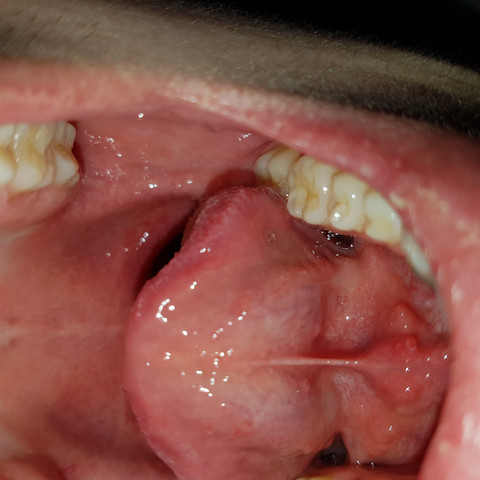

Mundboden Schwellung Denta Beaute